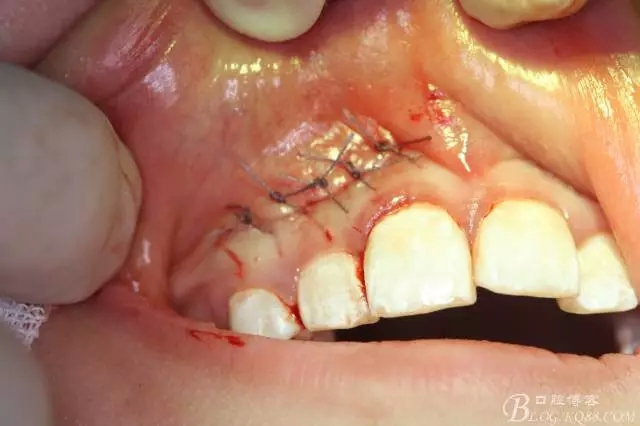

病例資料: 患者、柴xx、女、16歲。專科檢查及病歷如下圖: 患者同意我院正畸科建議,遂轉(zhuǎn)診倒外科。術(shù)前簽知情同意書。 治療過程: 圖1.術(shù)前的CBCT檢查:13阻生,疑為含牙囊腫。縱剖面顯示12牙根吸收至根尖1/3。 圖2.局部麻醉下 。行唇側(cè)弧形切口,12松動不到1°。 圖3.翻瓣、暴露骨面。 圖4.去骨、 暴露13牙冠 圖5.去骨、逐漸顯露13。 圖7.拔除13. 圖8.摘除囊壁 圖9.必須完整剝離囊壁。 圖10.摘除囊壁后形成的骨腔 圖11.超聲骨刀12根尖倒預(yù)備 圖13. 消毒棉球骨腔內(nèi)隔濕血液,紙尖干燥倒預(yù)備好的根管 圖14. 紙尖無血即可 圖15。MTA倒充填 圖16.骨腔填塞膠原蛋白海綿 圖17.拔除的13及摘除的囊壁 圖18.縫合 圖19.術(shù)后x線根尖片影像:MTA封閉根尖